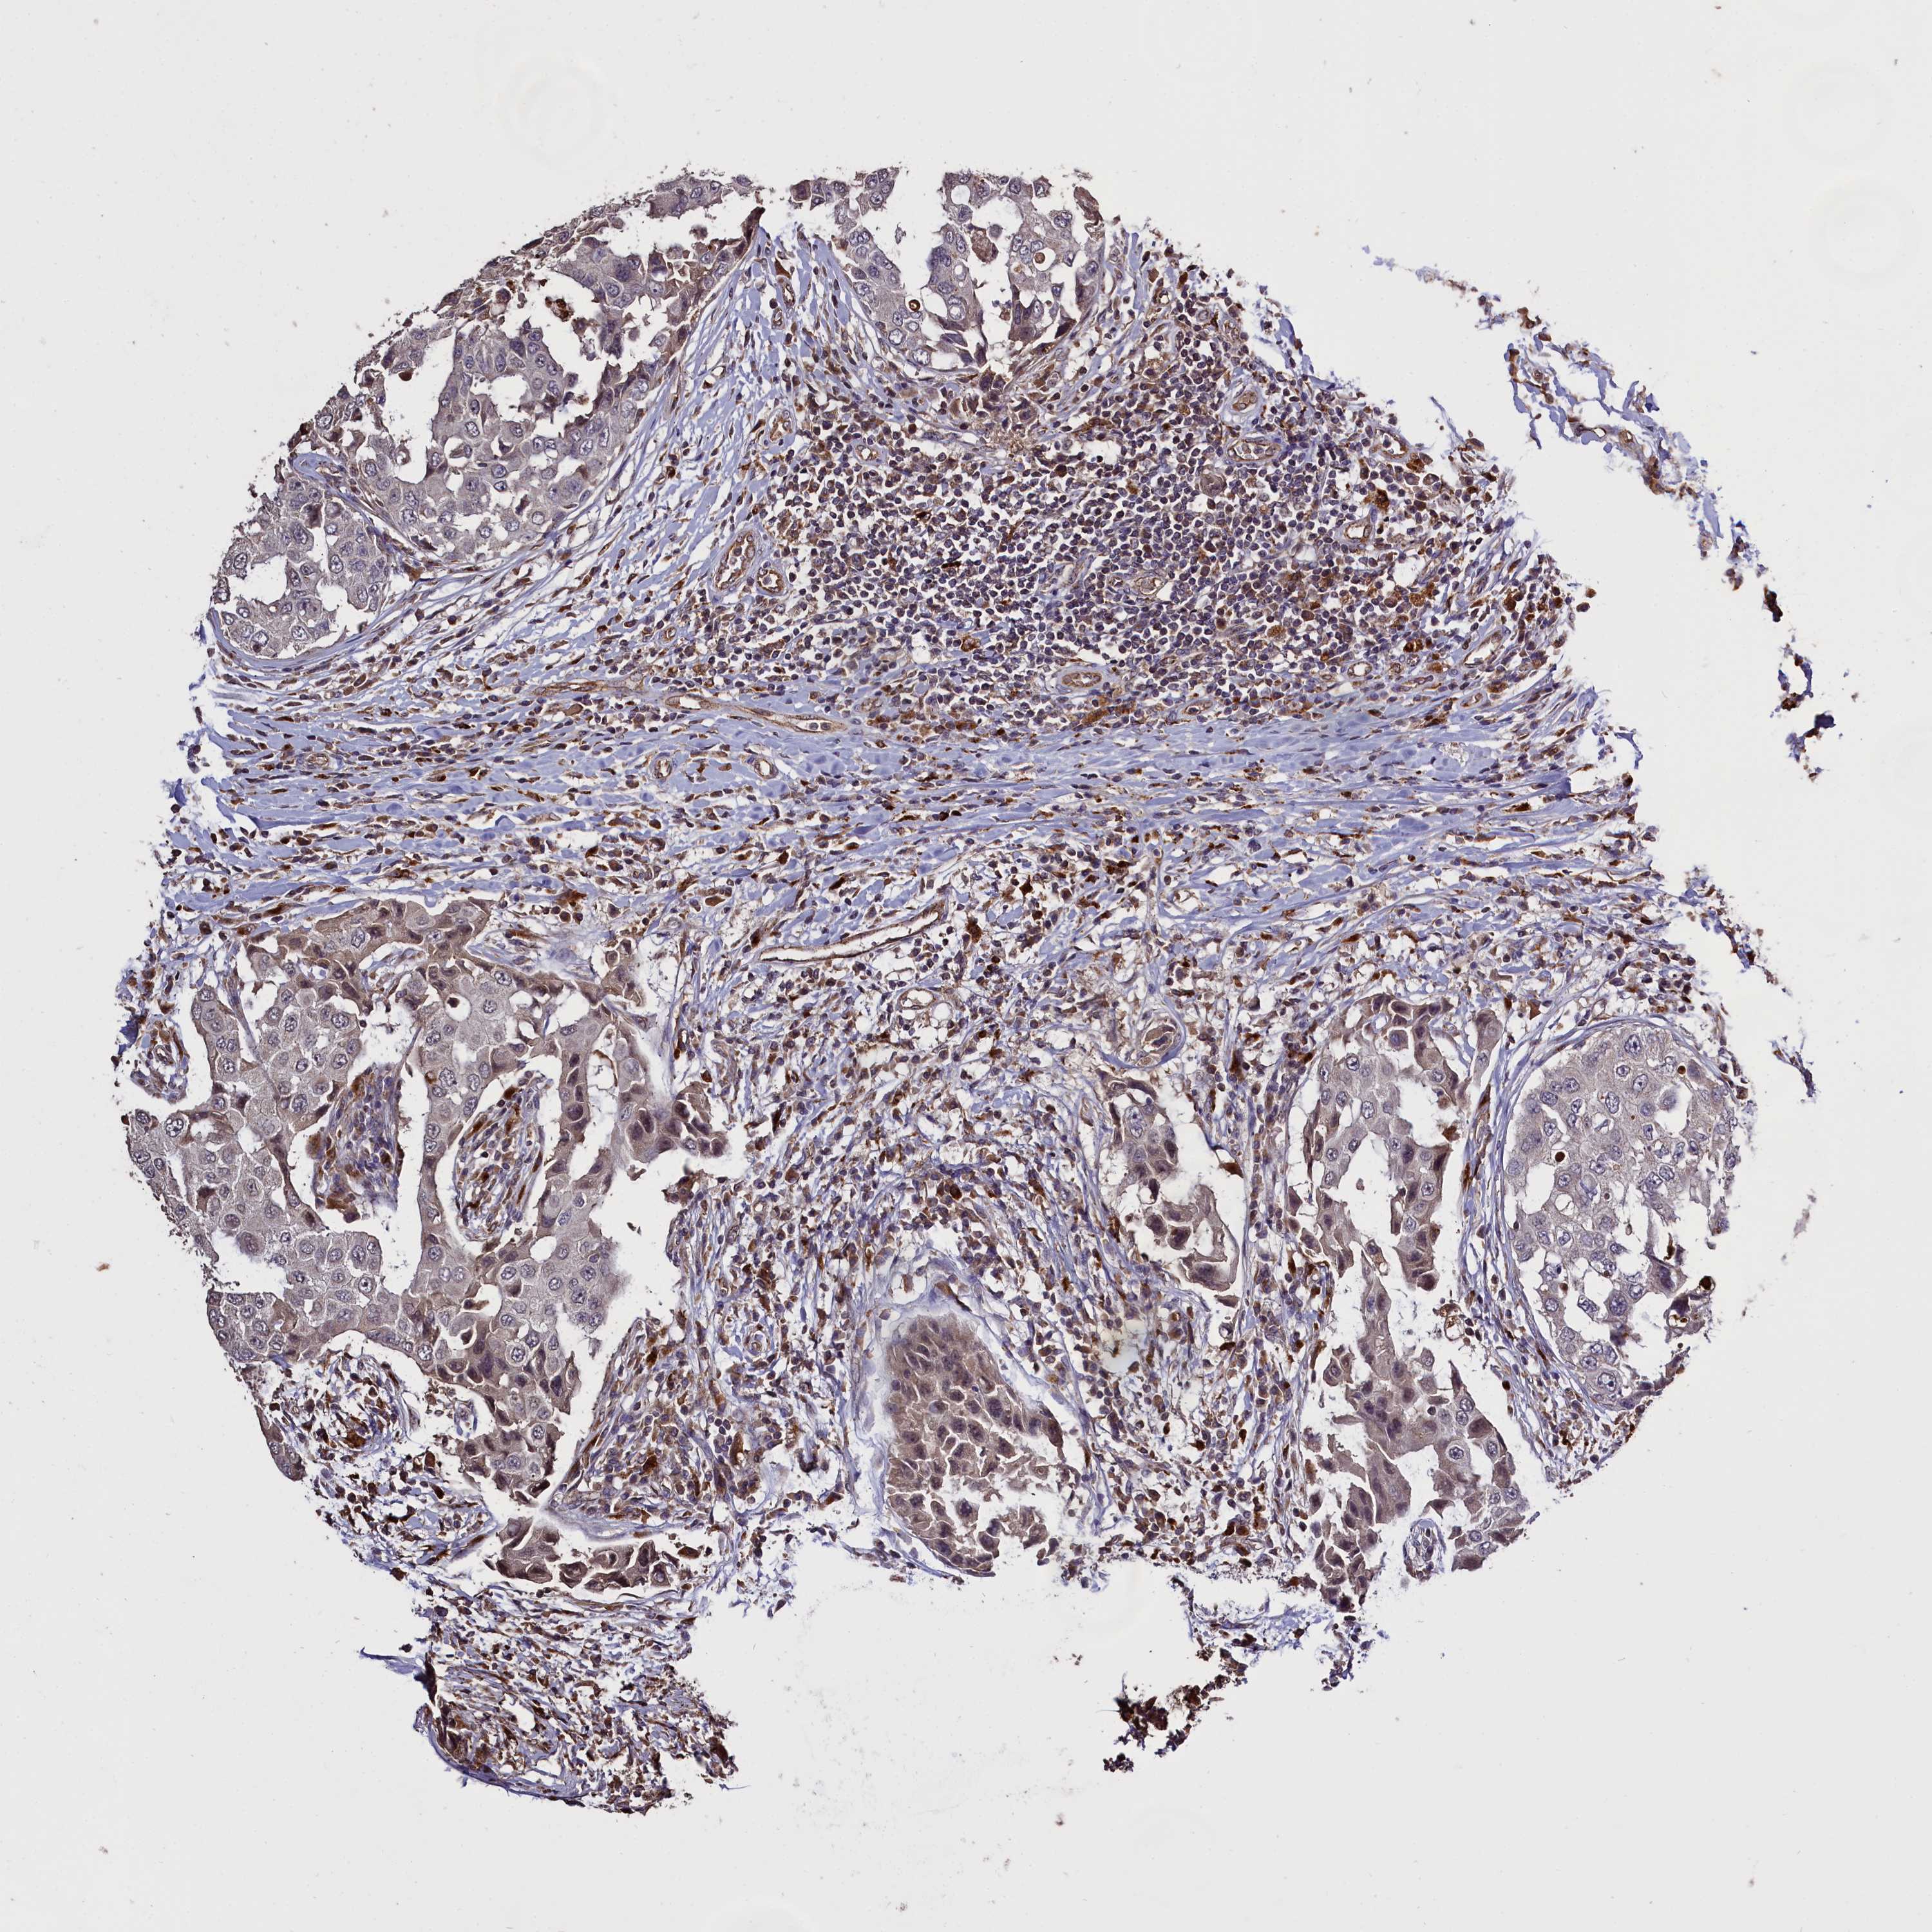

CANCER BREAST CANCER Show tissue menu

BRCA TCGA BRCA VALIDATION PROTEIN EXPRESSION

Breast cancer

Human cancer